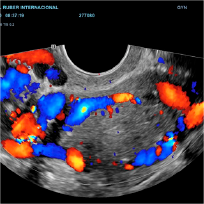

Ultrasonido Doppler